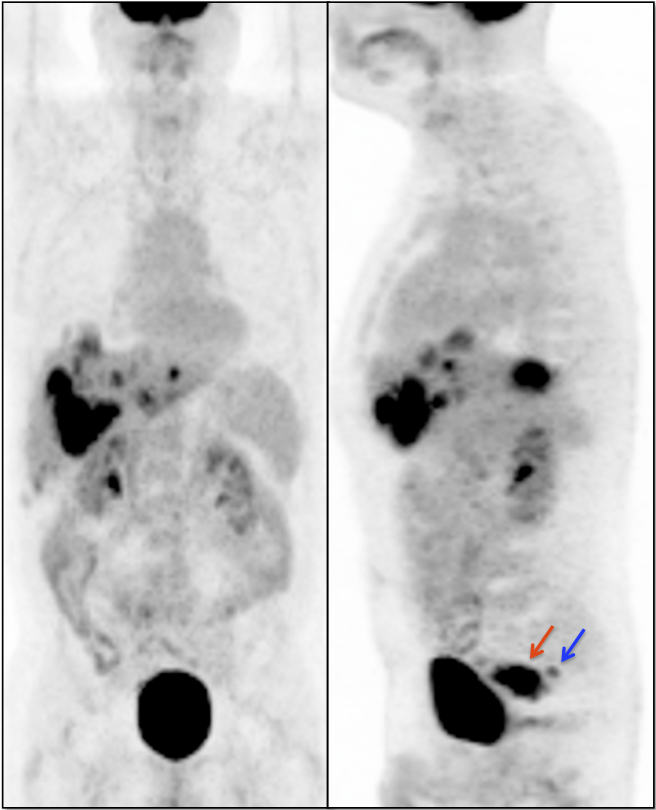

• Beware the small rectal cancer!  As the ano-rectal region frequently demonstrates intense physiologic uptake, it is very easy to overlook a rectal malignancy, especially if it is an incidental finding.  To avoid this error, always evaluate the rectum carefully on the sagittal whole body images.  It is shocking to see how readily apparent a rectal cancer can be on these images, yet so easily overlooked in the axial plane.